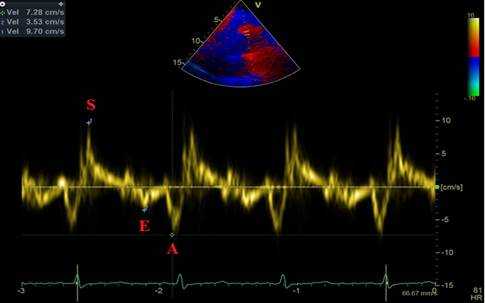

Анализ движения ближней стенки восходящего отдела грудной аорты проводится в режиме импульсно-волновой тканевой доплерографии с синхронной записью ЭКГ при задержке дыхания пациентом на протяжении 5-10 сердечных циклов. Контрольный объем размещается в области продольного среза восходящего отдела грудной аорты на участке на 3 см дистальнее фиброзного кольца аортального клапана при скорости развертки 50-100 мм/с. Точкой начала отсчета временных фаз считается первый антеградный систолический пик, соответствующий зубцу R ЭКГ. На каждом графике смещения доплеровских частот, отражающем скорости движения ближней стенки восходящего отдела грудной аорты, должны быть получены и выделены: S - скорость систолического смещения (см/с), А - скорость раннего диастолического смещения (см/с), E - скорость позднего диастолического смещения (см/с) (рис. 2).

Рис. 2. Левая парастернальная позиция по длинной оси на уровне 3 см выше аортального клапана, ИТД ближней стенки восходящего отдела аорты. S - скорость систолического смещения. Е - скорость раннего диастолического смещения. А - скорость позднего диастолического смещения